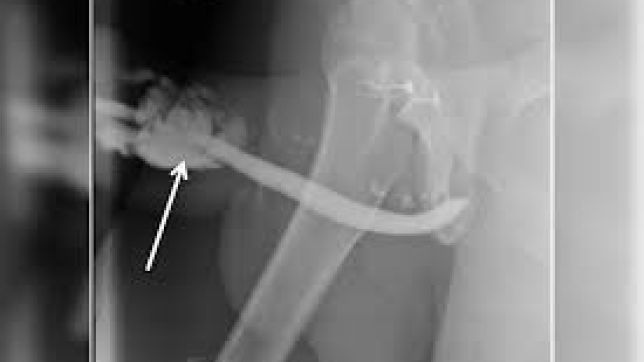

O paciente precisou passar por uma cirurgia de duas horas para retirar os pedaços da escova de dentes do pênis

Um homem de 43 anos, da Indonésia, precisou passar por uma cirurgia após uma escova de dentes quebrar dentro do pênis dele durante uma relação sexual. O objeto foi inserido no órgão sexual pelo próprio paciente.

Os médicos do Hospital Geral Acadêmico Soetomo, na cidade de Surabaya, contam que o homem esperou 12 horas para procurar atendimento médico. Ao chegar ao pronto-socorro, o pênis dele estava muito inchado e disforme.

O indonésio passou por uma cirurgia de duas horas e recebeu alta três dias depois. Na consulta de retorno, um mês depois, ele disse não ter sofrido complicações e conseguir urinar normalmente. O pênis também voltou ao formato original.